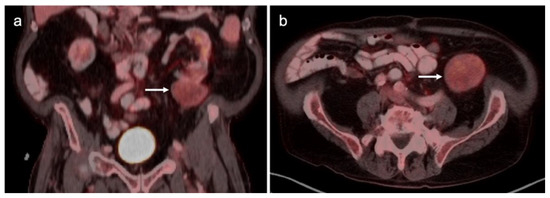

3.1. Prostate Cancer

3.2. Urothelial Carcinoma